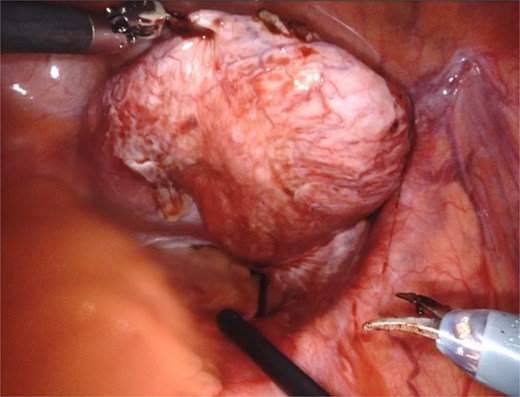

Based on the patient’s symptoms and imaging findings, robotic-assisted laparoscopic excision of the right seminal vesicle cyst was planned. The procedure was performed under general anesthesia using a da Vinci surgical system with a four-port approach. The patient was positioned in steep Trendelenburg position. A large right seminal vesicle cyst was identified posterior to the bladder (Fig. 2). Meticulous dissection was performed to separate the cyst from surrounding structures. The cyst contents were aspirated, yielding 150 cc of brownish fluid (Fig. 3). Complete excision was achieved while preserving the bladder neck, left ureter, and neurovascular bundles. Hem-o-lok clips were applied to secure the base of the cyst. Complete hemostasis was achieved, and there were no intraoperative complications.

An intraoperative image showing a large right seminal vesicle cyst identified posterior to the bladder.